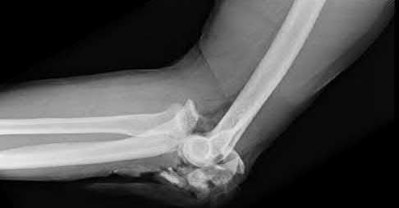

A patient has an elbow injury that includes a coronoid fracture, medial collateral ligament injury, and a radial head fracture. When is excision of the radial head without replacement indicated as definitive treatment for the radial head injury?

Excision is generally not indicated in this clinical scenario Corrent answer: 5

The injury likely represents a terrible triad injury. Restoration of the lateral column is required to restore valgus stability. A repaired or replaced radial head is also thought to be protective of the coronoid fracture repair. Therefore, excision is not indicated. Either radial head arthroplasty or open reduction and internal fixation would be indicated.